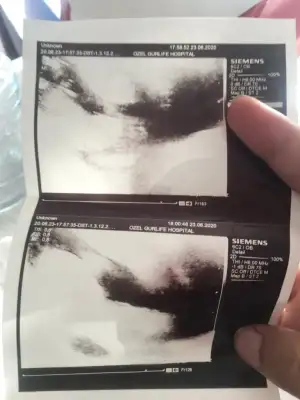

Kizlar merhaba 18haftalik gebeyim.dorduncu kez sormama ragmen doktorum cinsieti hakkinda asla kesin konuşmuyor özele gidiyorum.ister istemez uzuluyorum merak ediyorum her anne gibi haliyle...ultrason cihazida cok eski bebegi cektim diye bobregimi cekip veriyor sanki.Allahtan esim videoya almista ordan bi ss aldim.size atsam tecrubeli anneler tahmin edebilir misiniz?